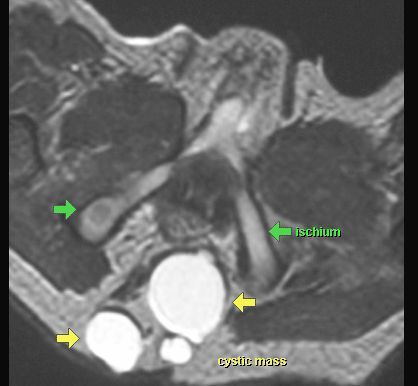

POTWORNIAK

MR